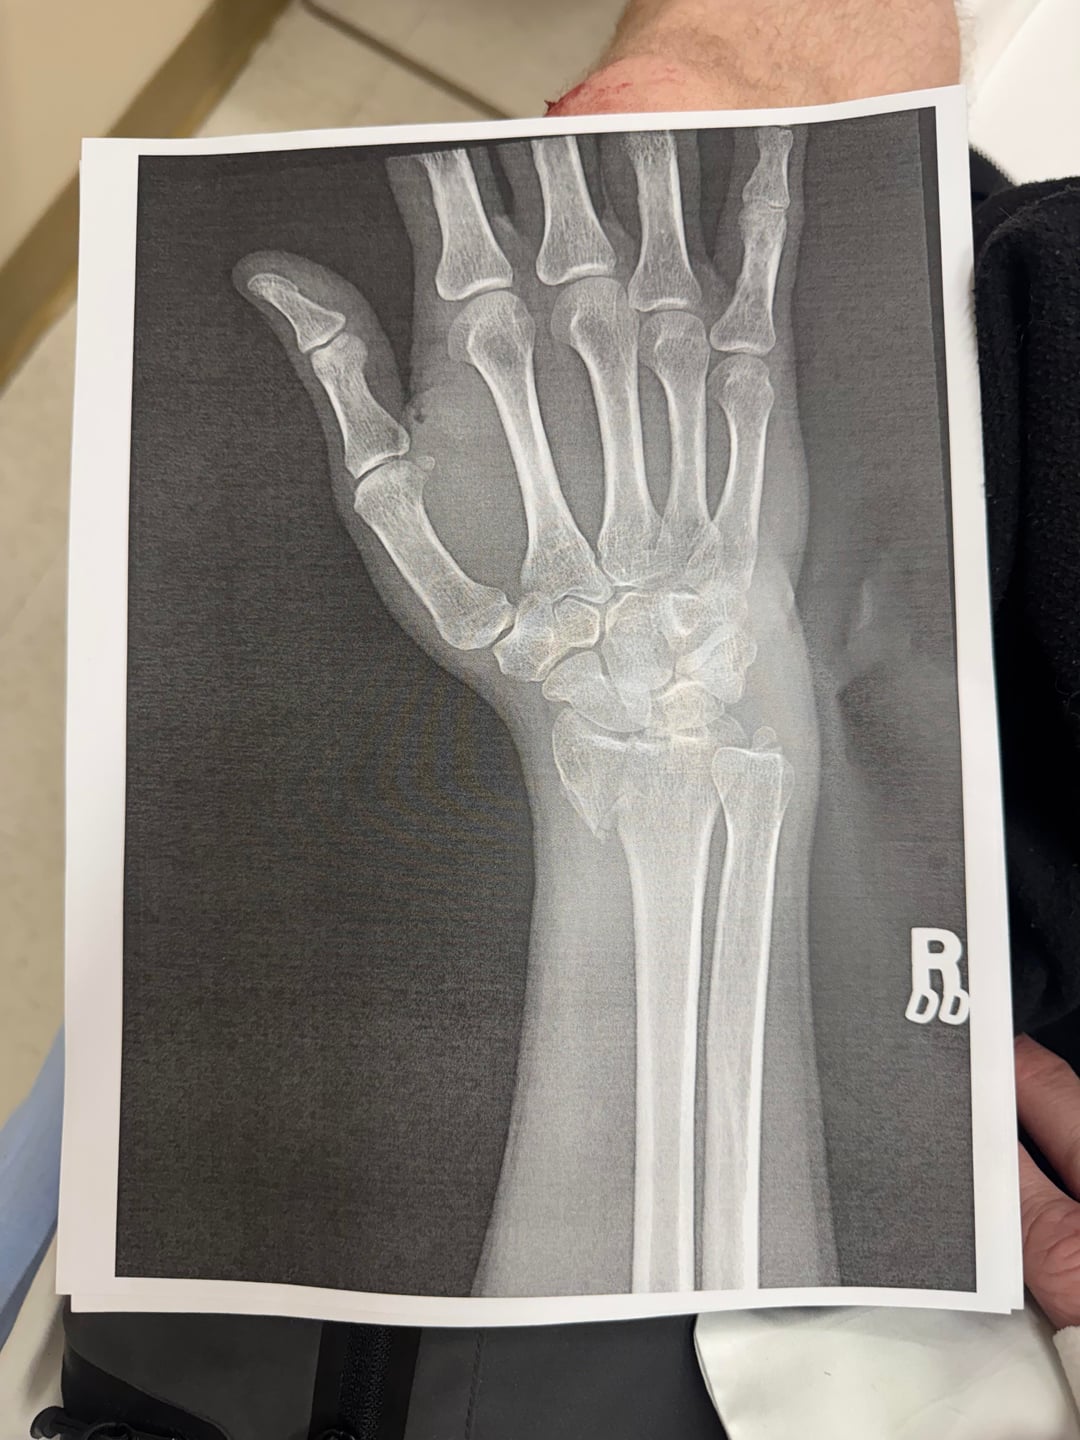

I went out to my local trail last night and tried to squeeze a ride in before it got too dark. It was going really well but I took a tricky corner over some roots too fast and ended up eating it. Now I’m waiting until tomorrow to call the hand specialist at my orthopedist since this will likely require surgery to repair.

Sorry man. Hopefully to put your mind at ease a bit: I had a worse break (I think) last year – head of radius in 6 pieces and totally misaligned; looks like you have one clean break. Will require surgery to put a plate in. I was back on the bike 4 months after the accident with surgeon permission.